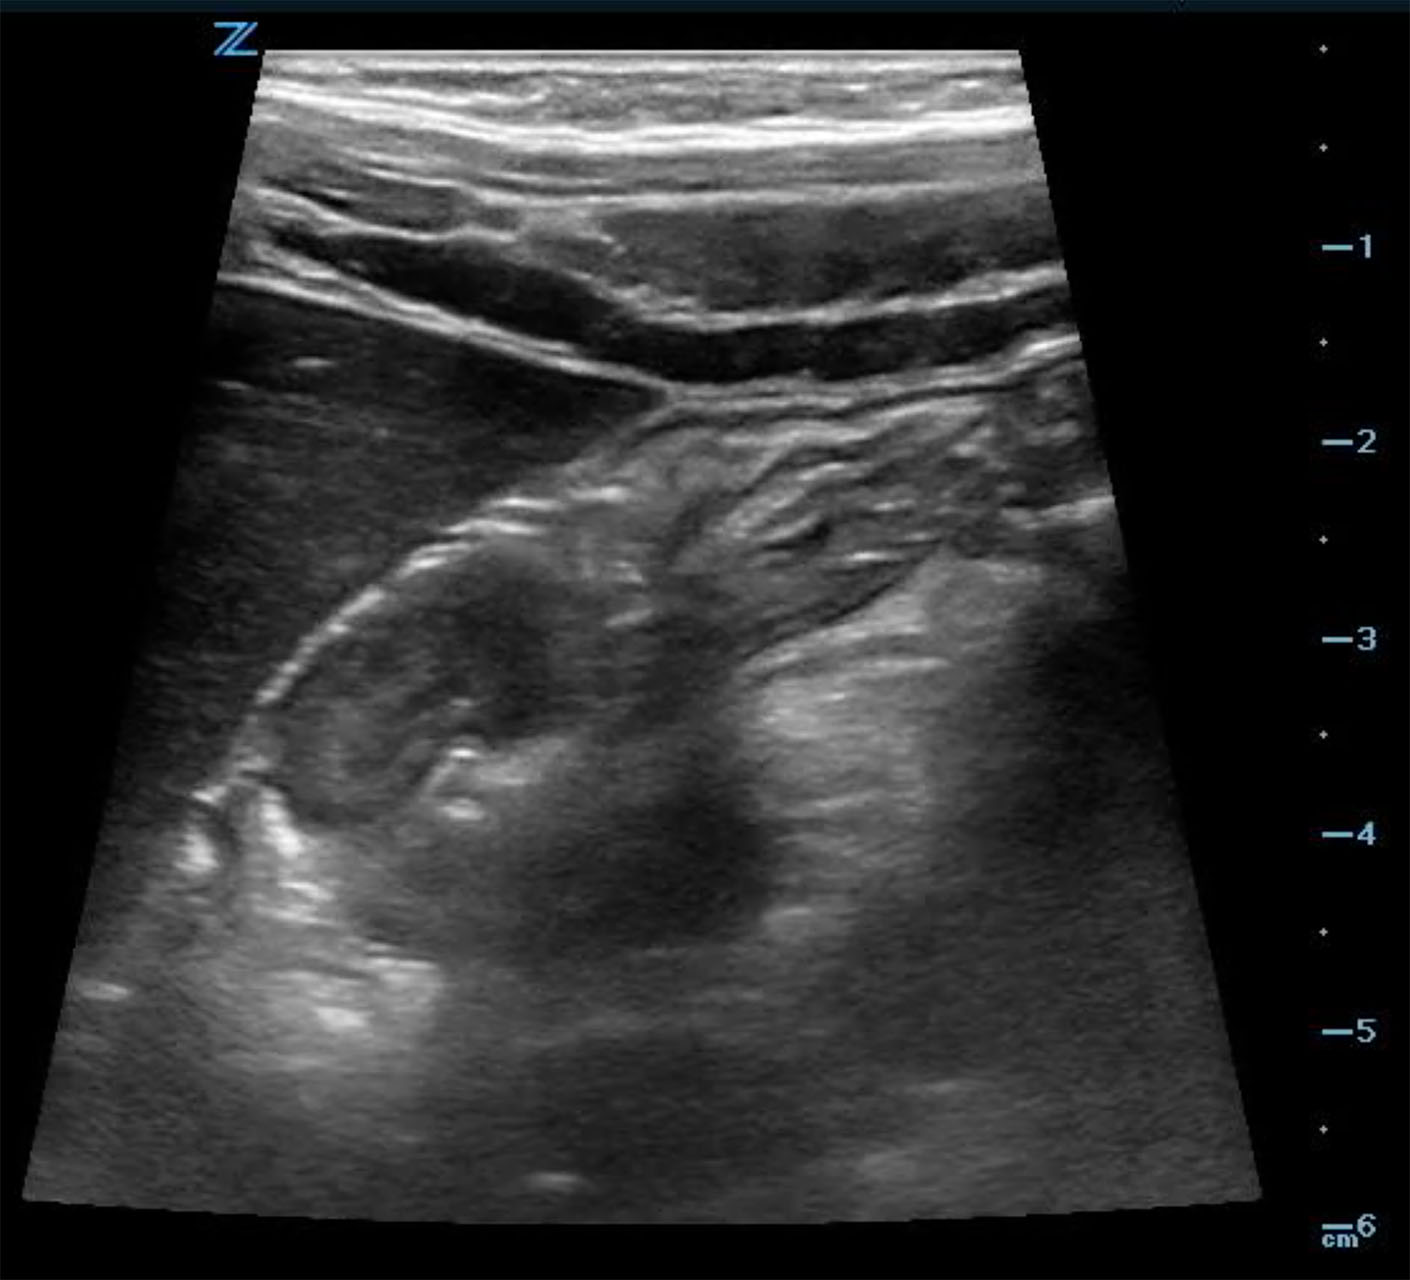

- When the intussusception is seen it should be imaged in both long (Fig. 6a, Video 3) and short (Fig. 6b, Video 3) axis.

- In the transverse axis, a target or doughnut sign, is seen. This is a cross sectional view of a mass made up of invaginated bowel intussusceptum and receiving bowel intussuscipiens, which creates the appearance of concentric rings. (Fig. 6b)

- Figure 6b. Image in short axis of ileocolic intussusception